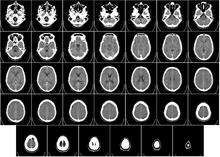

Head

CT scanning of the head is typically used to detect infarction, tumors, calcifications, haemorrhage, and bone trauma. Of the above, hypodense (dark) structures can indicate edema and infarction, hyperdense (bright) structures indicate calcifications and haemorrhage and bone trauma can be seen as disjunction in bone windows. Tumors can be detected by the swelling and anatomical distortion they cause, or by surrounding edema. Ambulances equipped with small bore multi-slice CT scanners respond to cases involving stroke or head trauma. CT scanning of the head is also used in CT-guided stereotactic surgery and radiosurgery for treatment of intracranial tumors, arteriovenous malformations, and other surgically treatable conditions using a device known as the N-localizer.[16][17][18][19][20][21]

Magnetic resonance imaging (MRI) of the head provides superior information as compared to CT scans when seeking information about headache to confirm a diagnosis of neoplasm, vascular disease, posterior cranial fossa lesions, cervicomedullary lesions, or intracranial pressure disorders.[22] It also does not carry the risks of exposing the patient to ionizing radiation.[22] CT scans may be used to diagnose headache when neuroimaging is indicated and MRI is not available, or in emergency settings when hemorrhage, stroke, or traumatic brain injury are suspected.[22] Even in emergency situations, when a head injury is minor as determined by a physician's evaluation and based on established guidelines, CT of the head should be avoided for adults and delayed pending clinical observation in the emergency department for children.[23]